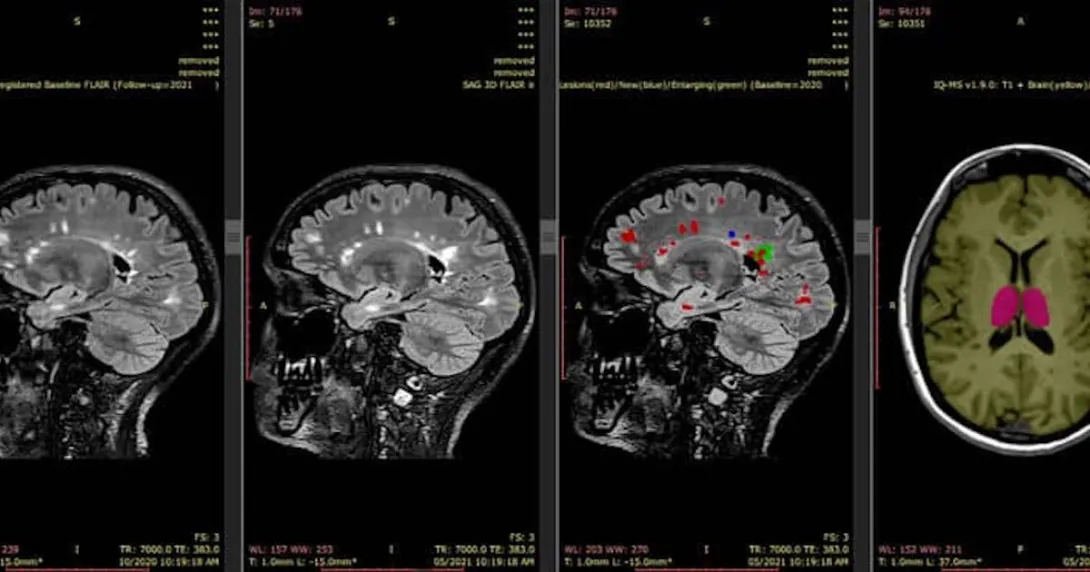

The funding will help scale and accelerate the commercialisation of its AI-enabled medical imaging software. iQ-solutions provides quantitative analysis of brain structures from MRI scans. It enables the precise and personalised monitoring and management of brain diseases, including multiple sclerosis and dementia.

"Our flagship tool, iQ-Solutions, supports radiologists to improve the detection and quantitation of new brain inflammation in patients with multiple sclerosis, which may prompt clinicians to recommend a change in therapy to prevent future disability," explained Michael Barnett, University of Sydney professor and co-founder of SNAC.